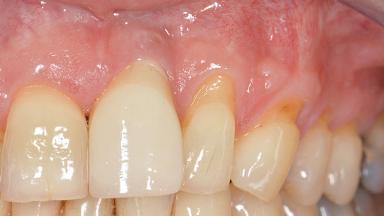

Treatment of Soft-Tissue Fenestration in the Esthetic Zone

This case demonstrates that a connective-tissue graft in combination with a coronally positioned graft is an effective method of treating cases with peri-implant mucositis and an abutment-level sinus abscess. A 42-year-old man presented with a swelling adjacent to an implant crown at site 21. The swelling had been present for approximately three weeks and was constrained to the buccal and palatal gingival aspects of the implant. A discharge was noted on finger pressure, with localized gingival recession present on the mid- and distolabial aspects of the crown.